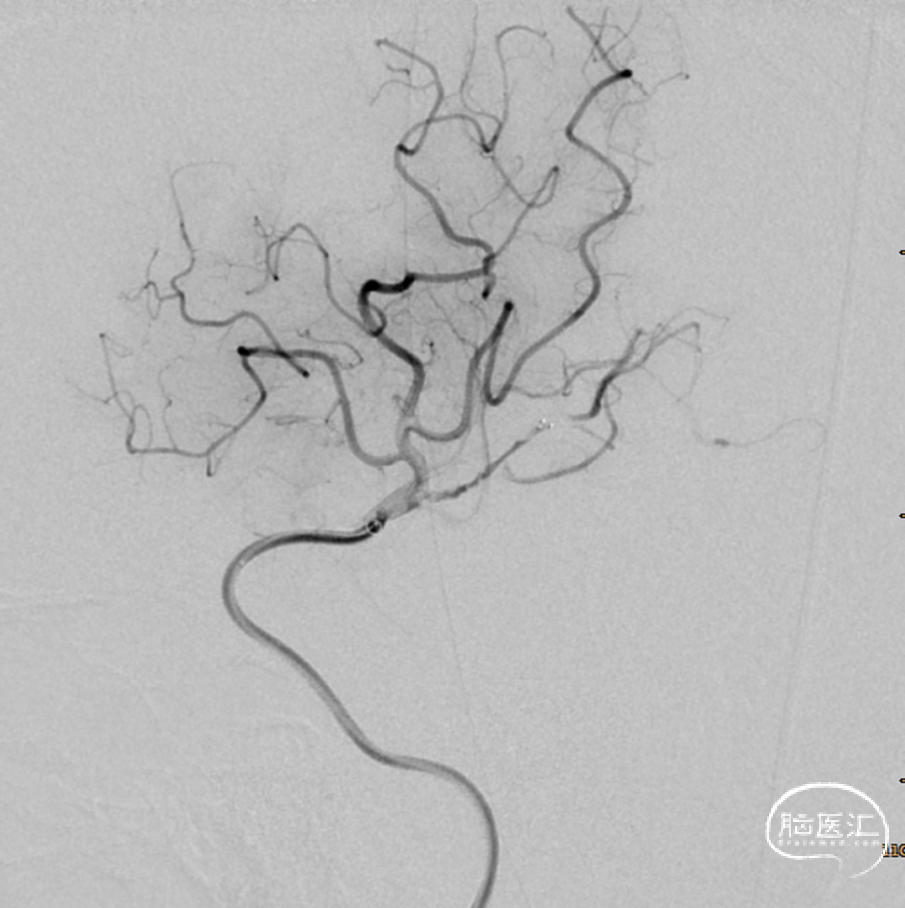

患者急性起病,最初起病NIHSS评分3分,最初头颅MRA可见LM1大血管闭塞,但仍有血管残端,结合DWI图像,考虑血栓在分叉部未完全堵塞血管;但后来患者突然加重,考虑侧枝衰竭或血栓位移或二次心源性栓塞可能性大(有房颤病史),计划首先ADAPT抽吸,再Solumbra技术抽拉结合取栓治疗,视情况必要时补充技术。

6F Neuron™ Max 90cm

CATALYST-6F*132cm

微导管(Rebar18)

微导丝(synchro-2,0.014*200cm)

Reco®3x20mm取栓支架

术后DynaCT,有少量造影剂外渗。予速尿针、白蛋白针、甘露醇针脱水预防脑水肿,阿司匹林肠溶片、抗血小板,强化他汀治疗。